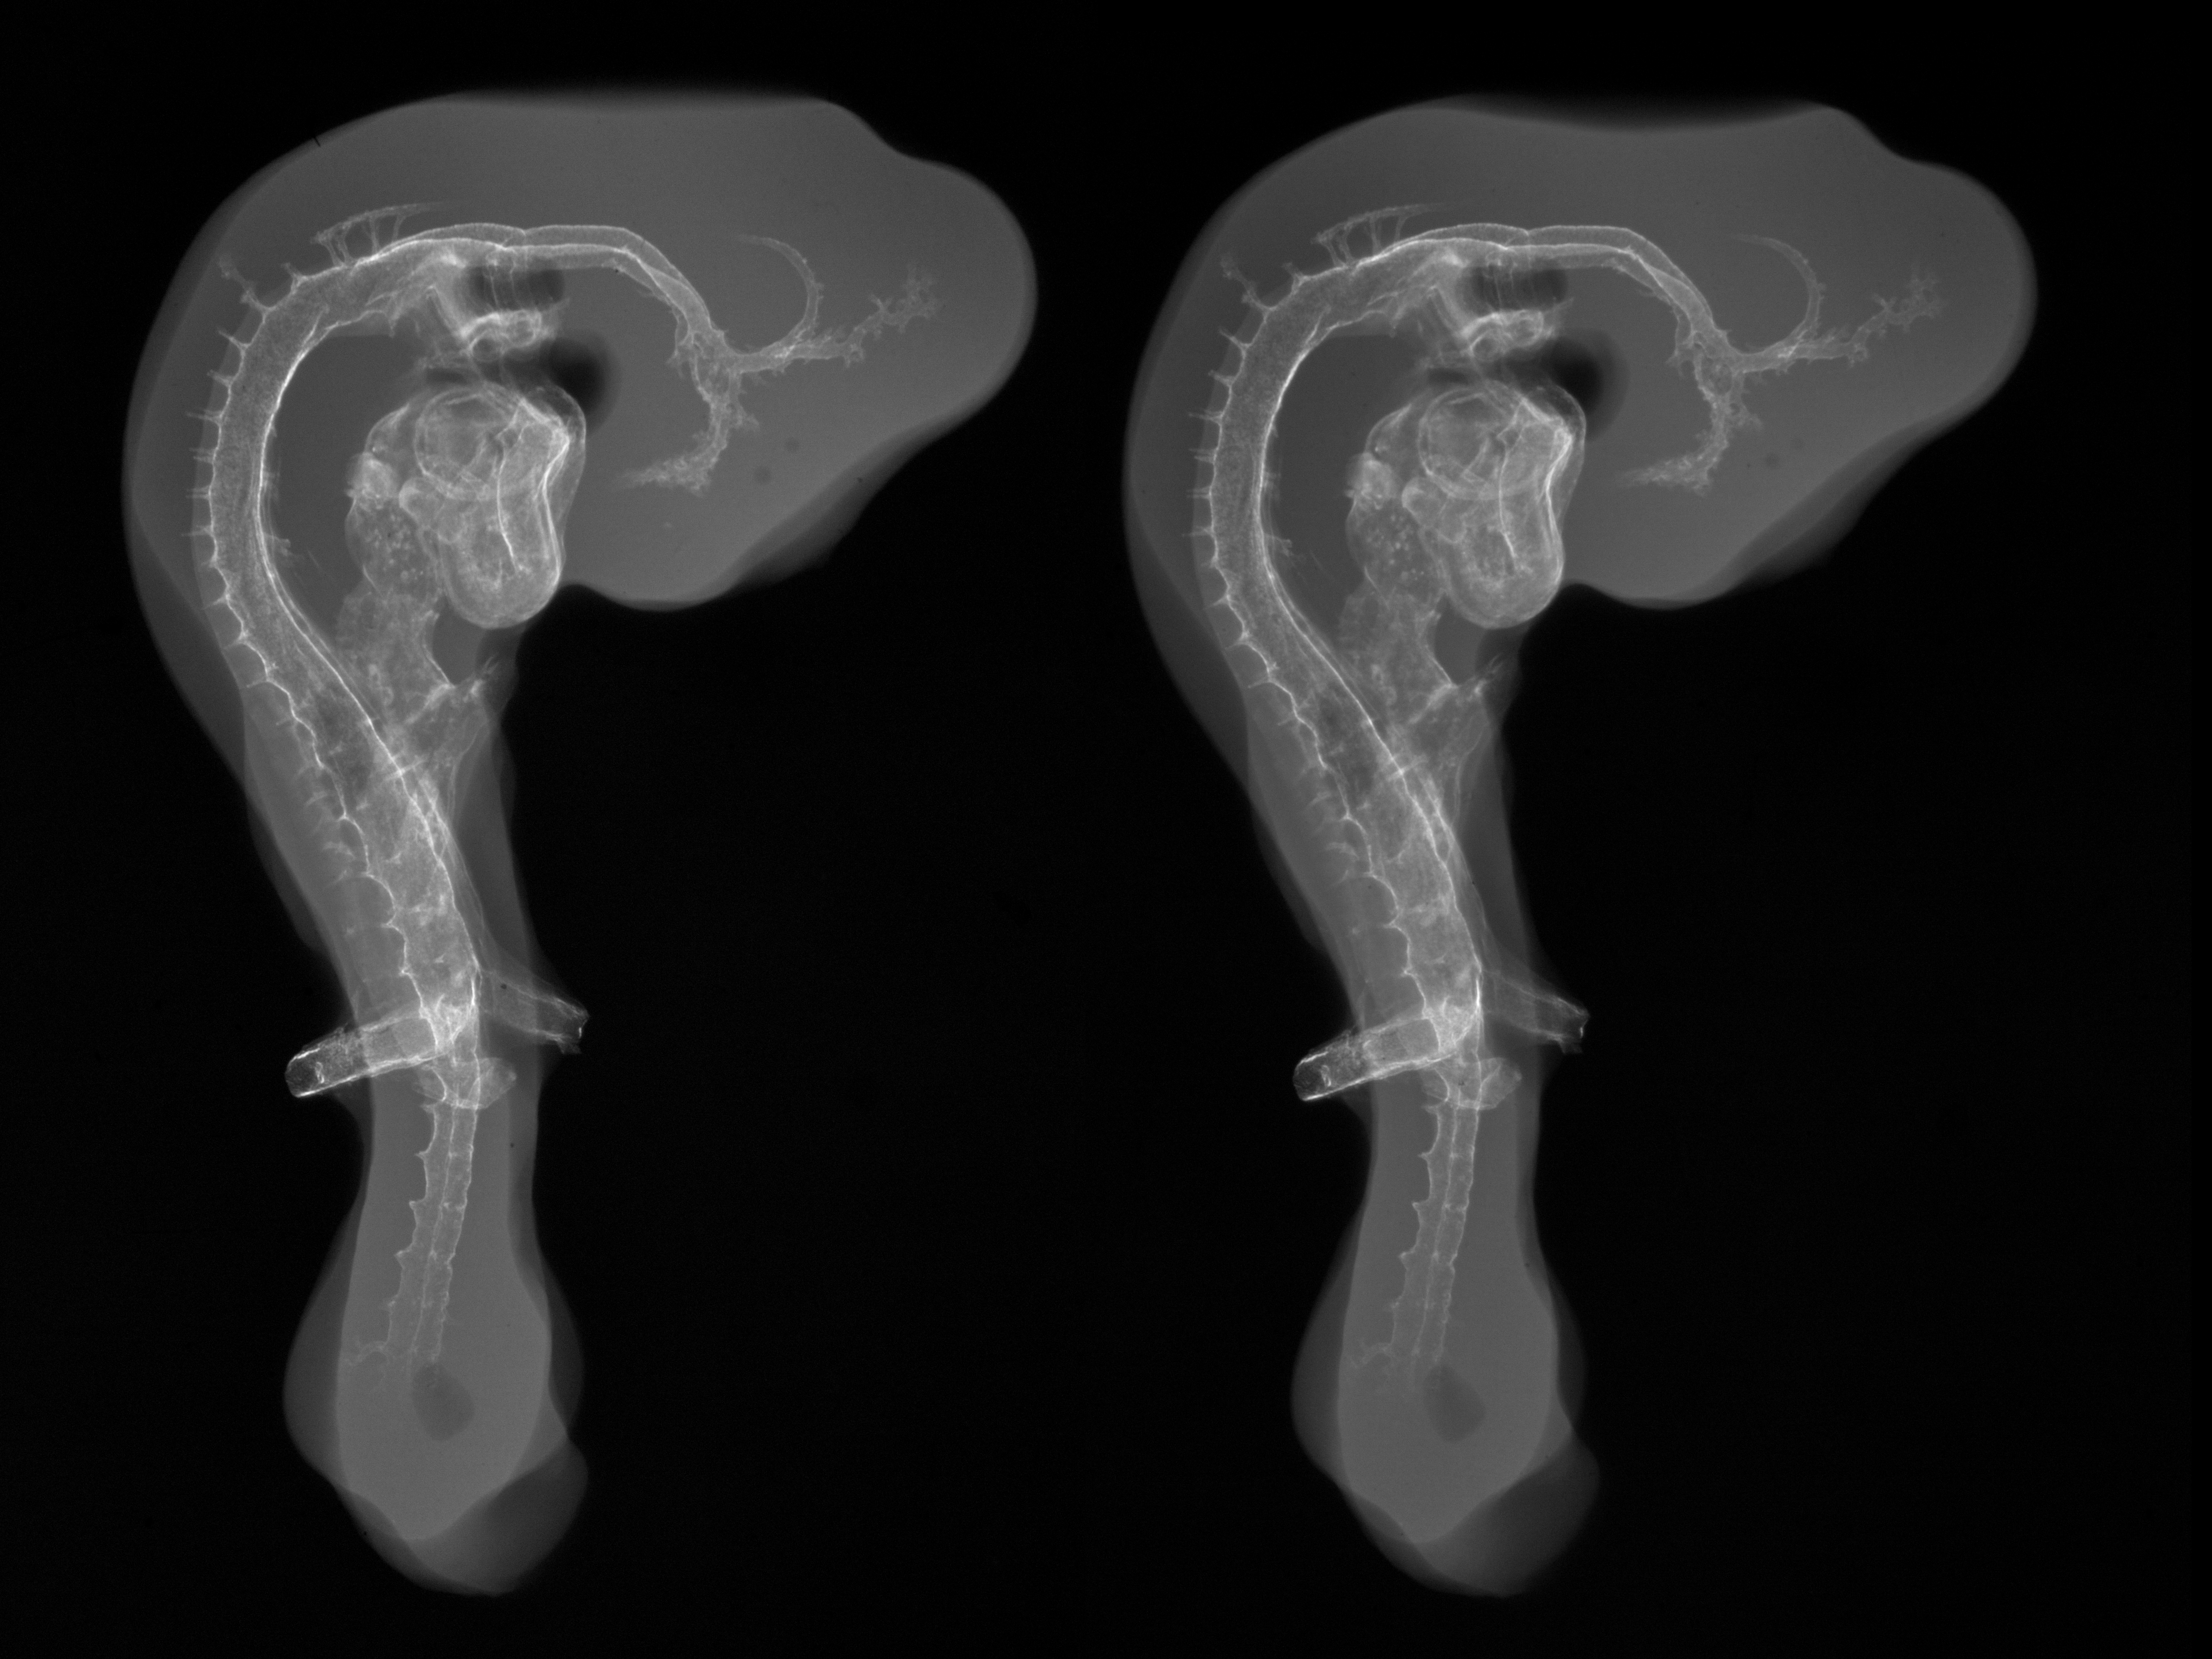

Chick Embryo Microangiography

Hamburger-Hamilton (HH) Stage 19 (approx. 3 - 3.5 days)

X-Ray Micrographs

Stereo X-Ray Micrographs